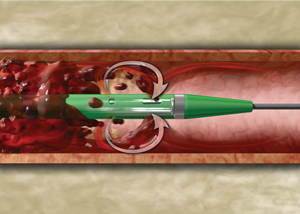

Mechanism of action

1. The AngioJet console monitors and controls the system.

2. The console energizes the pump which sends pressurized saline to the catheter tip.

Catheter illustration of procedure.

3. Saline jets travel backwards to create a low pressure zone causing a vacuum effect.

(Image 1)

Catheter moving through thrombus  in vein.

4. Thrombus is drawn into the in-flow windows and the jets push the thrombus back down the catheter.

(Image 2)